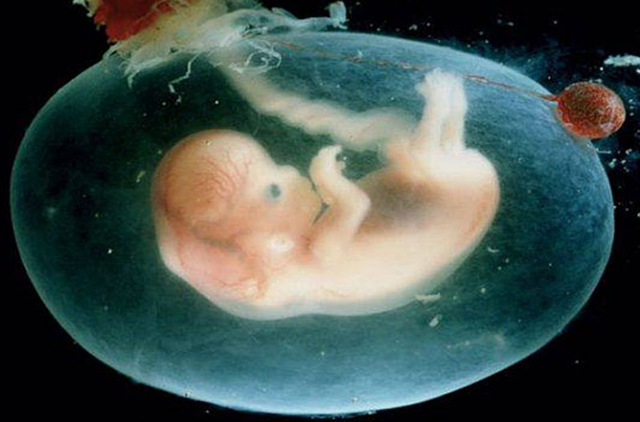

• Semana 9

Semana 9

En la 9 semana del embarazo tu bebé,que en este momento se conoce como feto, ahora que la cola del embrión ha desaparecido,en esta semana ya comienza a estirarse y enderezar su tronco y este bebe mide cerca de 2,5cm de largo.

• Semana 10

Semana 10

En la 10 semana del embarazo el bebe ya a pasado de embrión a feto .Y es que va a haber mucho cambiado en su desarrollo se comienza a ver muy claramente que es un ser humano a simple vista por su tamaño y peso.Las medidas del bebé rondan los 4 centímetros y su peso es de 5 gramos.